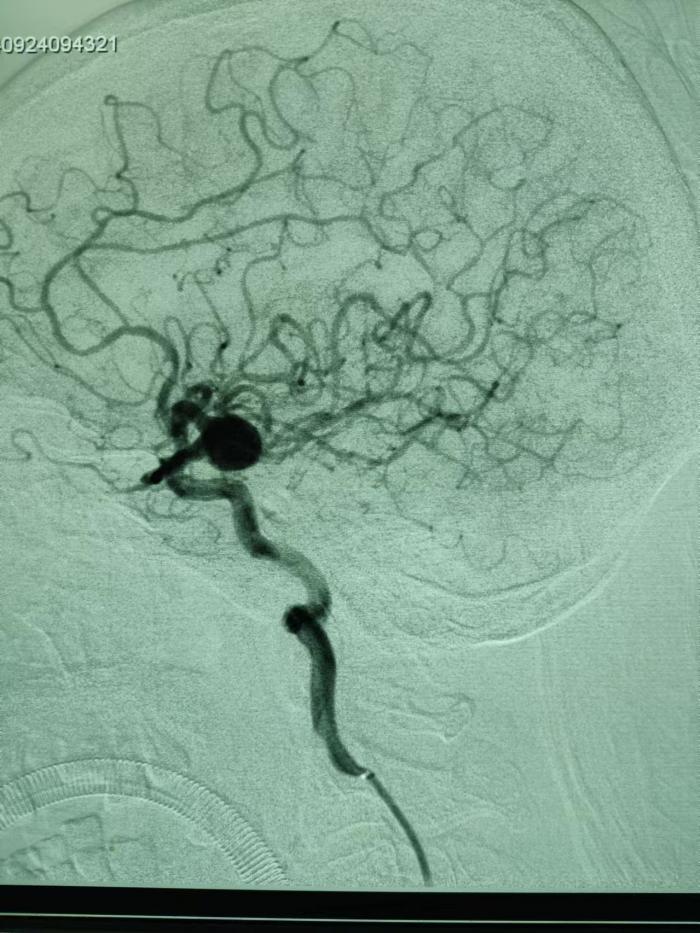

郴州市的唐爷爷今年71岁,因反复头晕1月余,在神内二科住院治疗,入院后经全脑血管造影术发现,左侧颈内动脉有10mm*12mm大动脉瘤。“动脉瘤就像一个隐形炸弹,随时有可能发生破裂,一旦破裂必将危急患者生命,需实施手术治疗。”神经内二科主任陈雁斌说。经过全院多学科会诊后,科室为患者制定了详细的治疗方案,决定采用介入治疗方式在老人颅内置入血流导向装置(密网支架),为患者健康保驾护航。

手术在全麻下进行,医务人员采用Seldinger穿刺技术经右侧股动脉,置入6F长鞘,在路图指示下,将支架导管固定妥善,随后将血流导向装置准确的释放在颈内动脉c7段,完全覆盖瘤颈,顺利完成手术操作。术后复查未见异常,置入血流导向装置(密网支架)后,动脉瘤内血运被阻断,将逐渐萎缩,威胁唐爷爷生命安全的炸弹就此解除,患者及家属对手术效果赞不绝口。